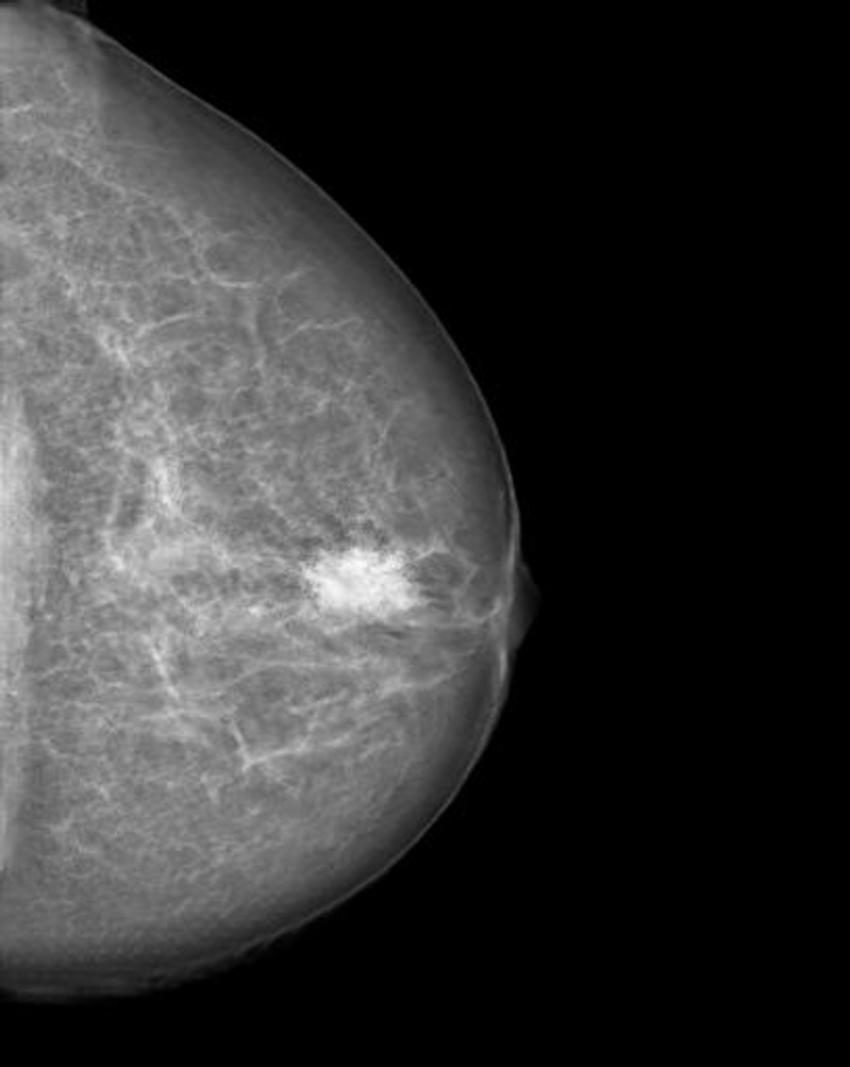

The researchers trained a cycle-consistent generative adversarial network (CycleGAN), a type of artificial intelligence application, on 680 mammographic images from 334 patients, to convert images showing cancer to healthy ones and to do the same, in reverse, for the normal control images. They wanted to determine if a CycleGAN could insert or remove cancer-specific features into mammograms in a realistic fashion.

The images were presented to three radiologists, who reviewed the images and indicated whether they thought the images were genuine or modified. None of the radiologists could reliably distinguish between the two.

"Neural networks, such as CycleGAN, are not only able to learn what breast cancer looks like," Dr. Becker said, "we have now shown that they can insert these learned characteristics into mammograms of healthy patients or remove cancerous lesions from the image and replace them with normal looking tissue."

Figure 1. Mammogram of a healthy breast.

Figure 2. Manipulated mammogram of breast in Figure 1 with a neural-network-generated mass.